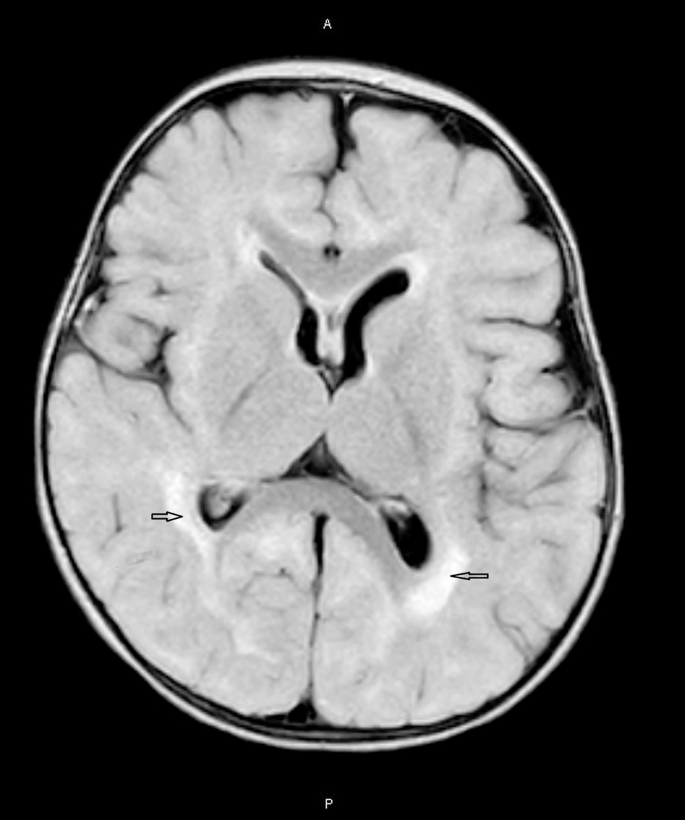

她是足月出生的,出生时即有巨颅症(头围36.8厘米,第99百分位)。EEG显示异常节律并记录到癫痫性痉挛,确诊为IESS(见图1)。脑部MRI显示双侧脑室周围白质信号异常,但没有皮质发育不良或大脑肥大的表现(见图2)。全外显子测序发现她携带一个杂合的PTEN变异,位于外显子6的c.509G > A(p.S170N)(基因序列:NM_000314.4),该变异来自她的母亲。根据美国医学遗传学与基因组学学院(ACMG–AMP)的指南,该变异被归类为“可能致病性”变异:基于“致病性中等1型(PM1,位于PTEN关键功能域)”、“致病性中等2型(PM2,未在人群数据库中收录)”以及“致病性支持3型(PP3,计算机预测具有有害效应)”。此外,“致病性支持5型(PP5,此前在PTEN相关表型中也有报道)”也被考虑在内。常规EEG显示发作间期的异常节律,Burden of Amplitudes and Epileptiform Discharges(BASED)评分为5分。箭头指示的癫痫性痉挛表现为δ波短暂放电后跟随电极电位下降,确诊为婴儿癫痫性痉挛综合征(IESS)。